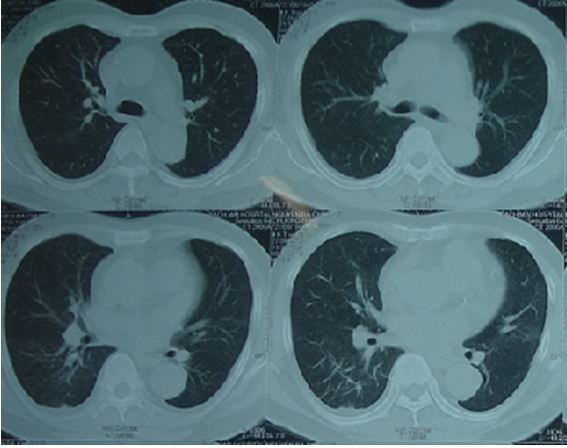

Bệnh nhân được chụp cắt lớp vi tính lồng ngực cho thấy hình ảnh dày tổ chức kẽ thùy dưới phổi phải, không thấy tổn thương di căn

Hình 2. Hình ảnh chụp cắt lớp vi tính (CT) lồng ngực